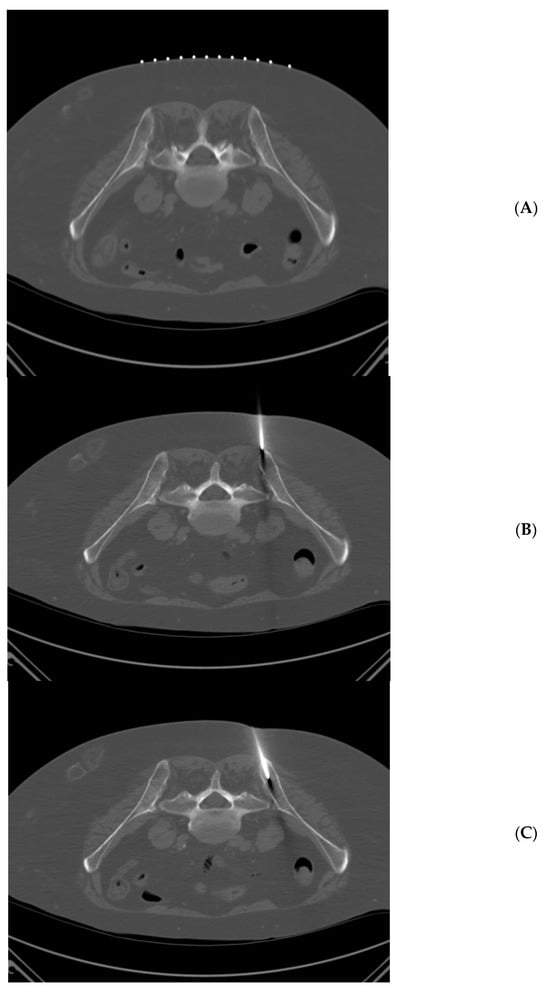

Figure 2.

65 year-old woman with multiple myeloma. Technically successful biopsy, with adequate pathology results. (A) Prone position pre-planning CT with skin guidance markers on the left side of the patient. (B) Prone position CT with biopsy needle tip approaching left posterior iliac spine. (C) Prone position CT with biopsy needle tip within the left posterior iliac spine.